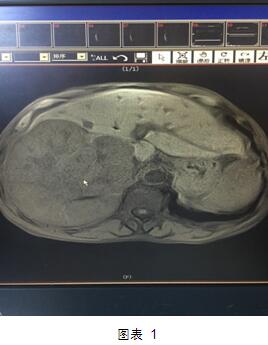

但是近日,我院肝膽外科就做了一次這樣的大挑戰(zhàn)?;颊呤且晃?0多歲的老者,老人家入院后診斷為肝右葉巨塊型肝癌(圖1)。這個(gè)癌塊已經(jīng)占據(jù)整個(gè)肝臟的60%,而且腫瘤侵及第一肝門、第二肝門,門靜脈有癌栓形成。這種情況在臨床上已經(jīng)屬于中晚期肝癌,手術(shù)根治困難,風(fēng)險(xiǎn)極大。然而不手術(shù)切除的話,老人家的生存期恐怕不會(huì)超過三個(gè)月,而且會(huì)一直處于癌癥的折磨之中。